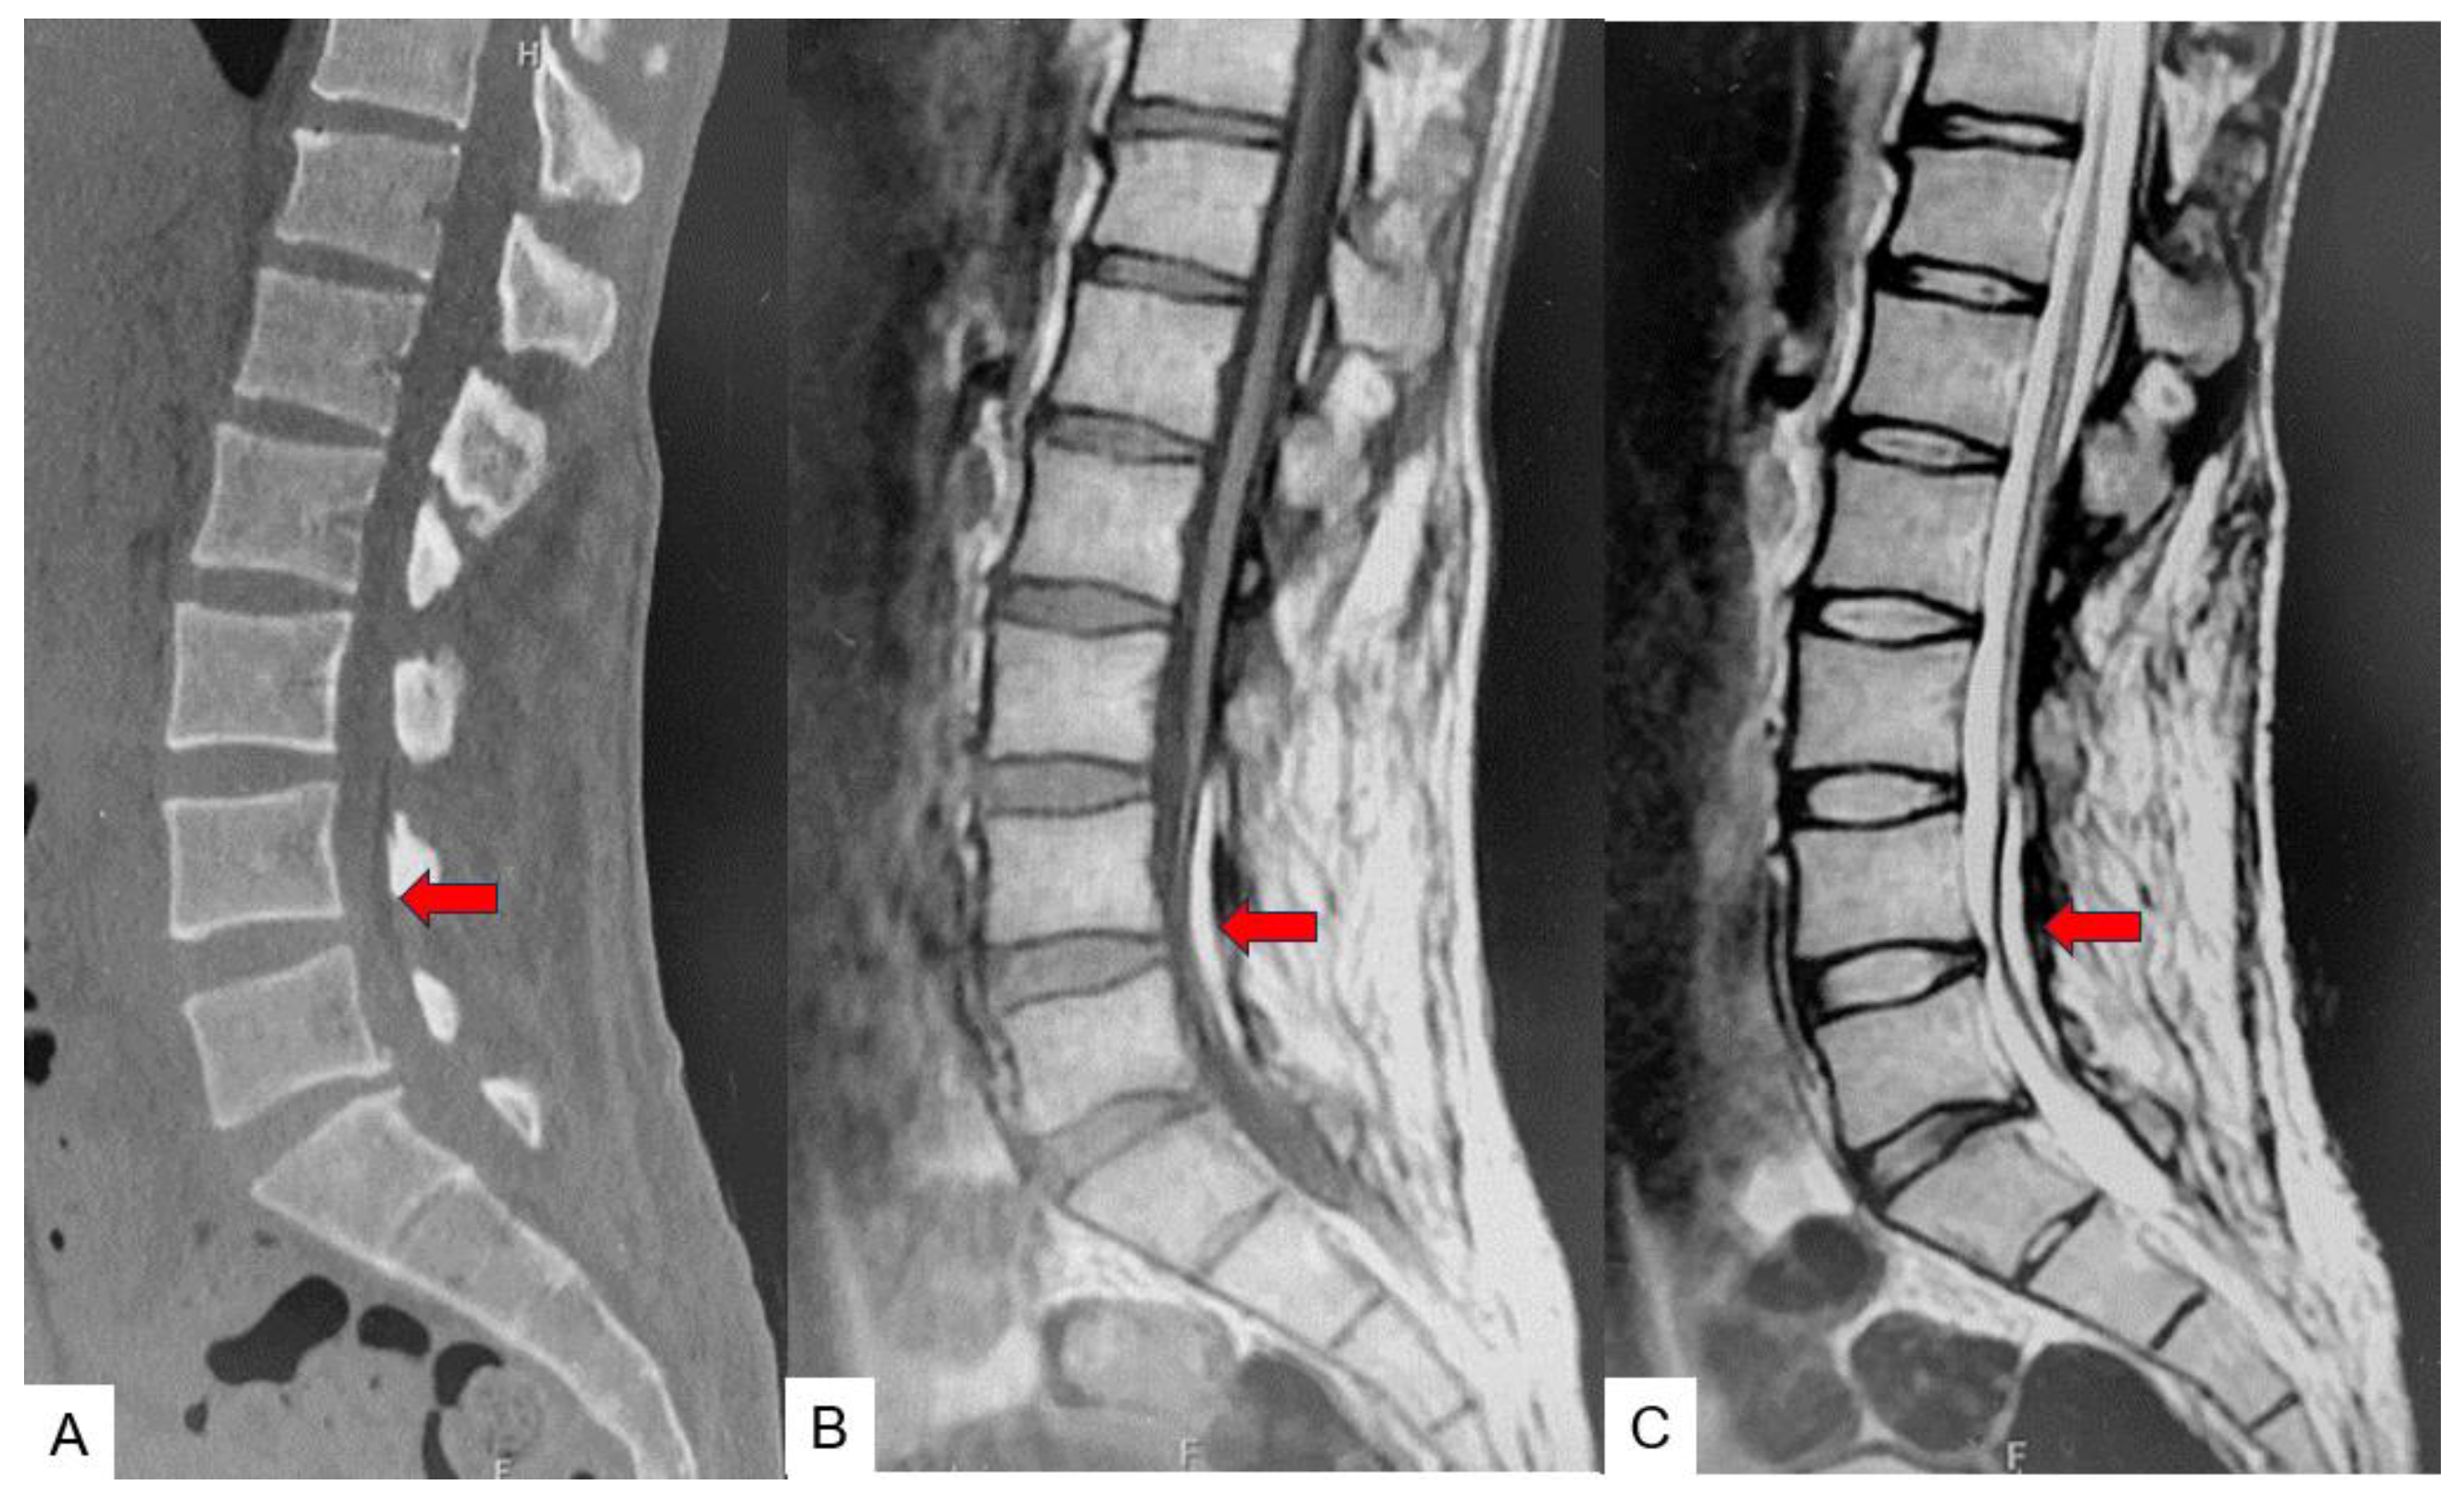

2. Case 1 31 years old male, tethered cord syndrome

2.3. Preoperative imaging